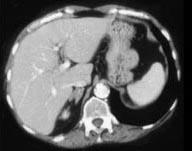

问题 女,42岁,夜尿增多伴高血压,实验室检查:血和尿醛固酮水平增加,请结合图像,选择最佳答案 ( )

选项 A、双侧肾上腺转移瘤 B、双侧肾上腺淋巴瘤 C、双侧肾上腺腺瘤 D、双侧肾上腺未见异常 E、双侧肾上腺增生

答案 E